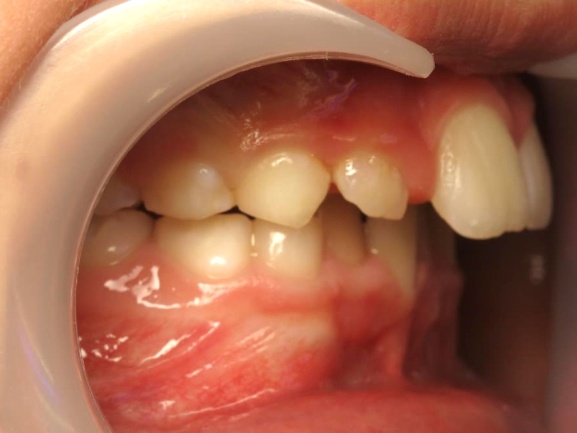

2 - Phase 1: Correction du décalage des mâchoires

Ce type de traitement, au résultat visuellement impressionnant, n’est possible que lorsque le problème vient du maxillaire supérieur trop en avant. Si c’est au contraire la mâchoire inférieure qui n’a pas assez grandi, le traitement est plus complexe et nécessite souvent une approche combinée orthodontie-chirurgie.